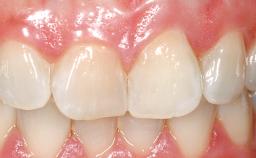

A 30-year-old female patient had lost tooth 21 and was referred to our clinic for consultation and treatment. Due to advanced apical infection, tooth 21 had been extracted two months earlier at another clinic and an acrylic-resin tooth had been bonded to the adjacent teeth. The patient desired implant treatment to avoid any damage to the adjacent natural teeth. While the patient had no history of any systemic disorder, she was a heavy smoker and exhibited medium to advanced periodontitis in the entire jaw. After the initial treatment to achieve a pocket probing depth of less than 4 mm and no bleeding on probing, a decrease in the height of the papillae mesial and distal to the extraction site and overall gingival recession were observed.

Prosthesis Type FDP

Retention Cemented, with meso-structure Cemented, with meso-structure

Provisional Implant-Supported Prosthesis Prosthodontic margin < 3 mm apical to mucosal margin Prosthodontic margin < 3 mm apical to mucosal margin